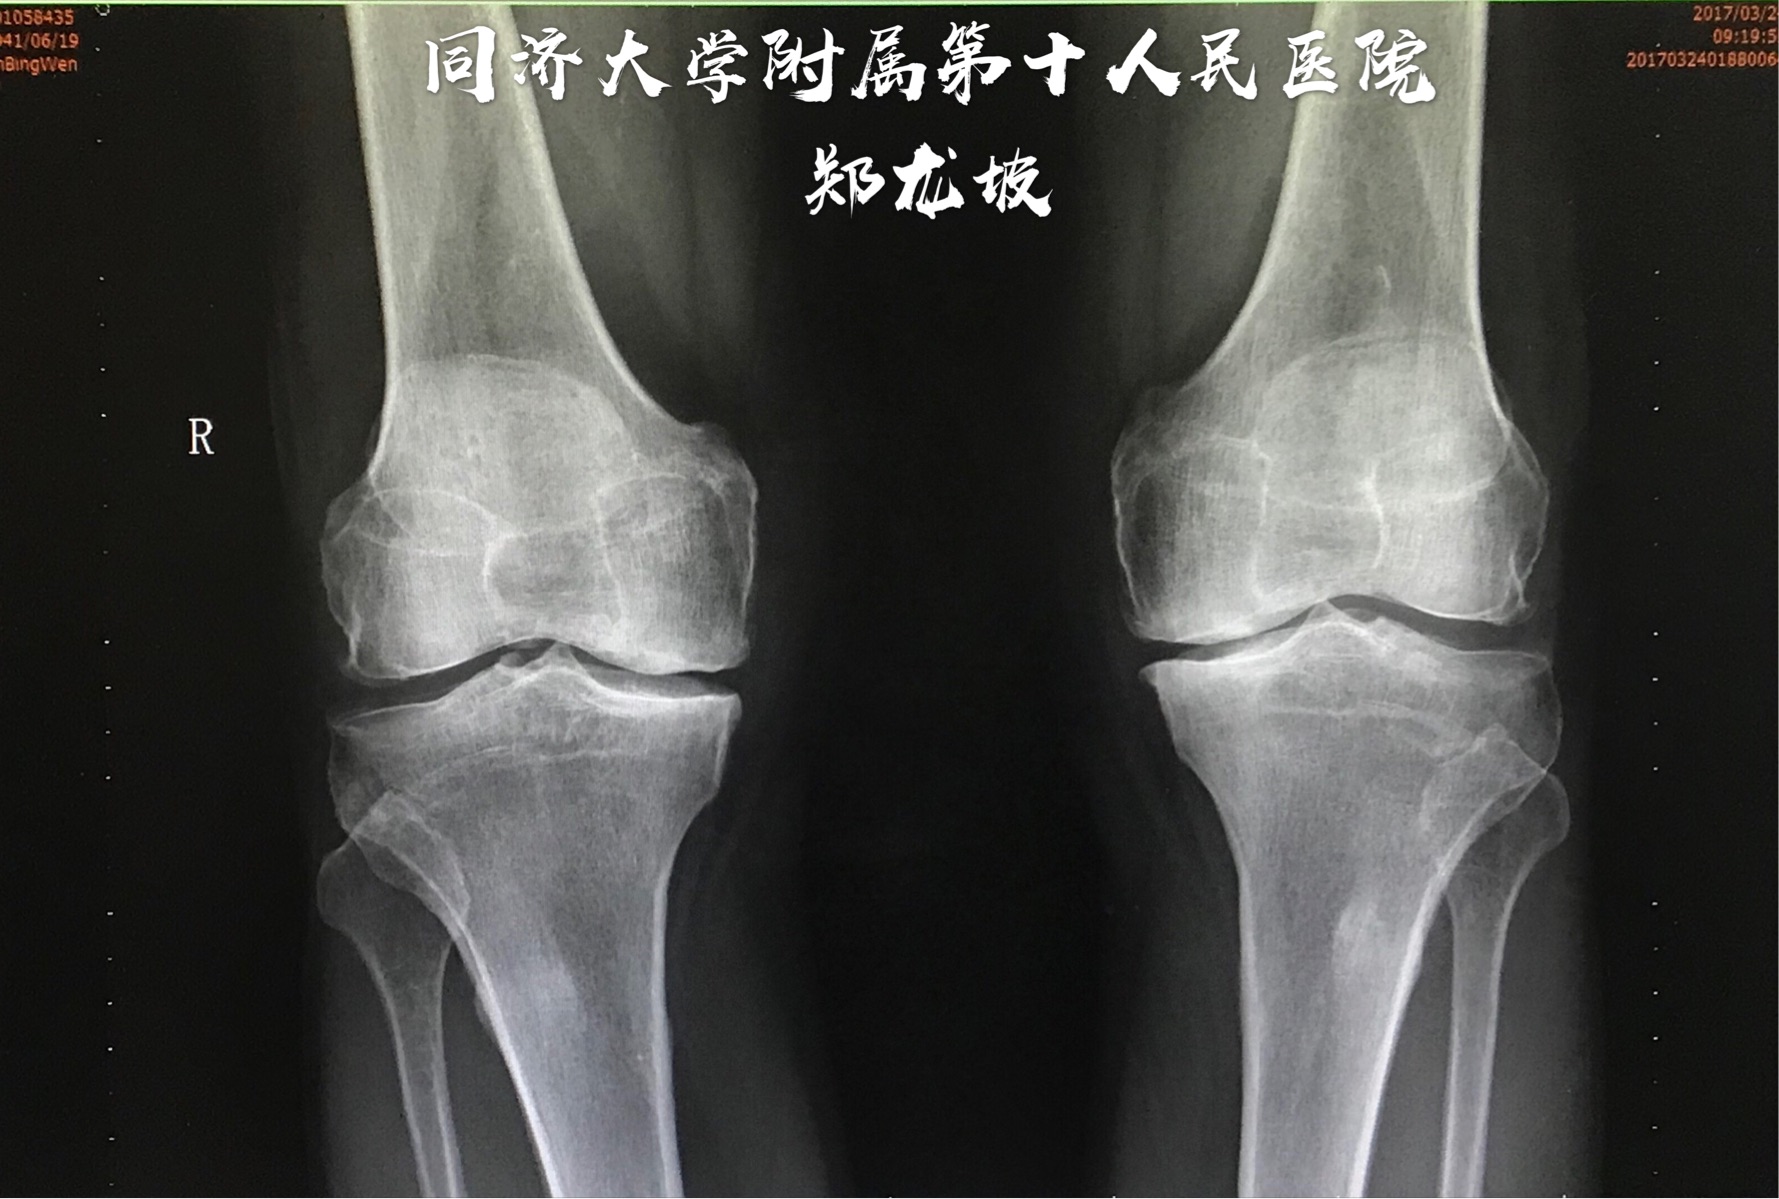

我有一个治疗膝关节炎的效方,用了很多年,临床上疗效显著,特献出来与大家共勉,请广大博友验证。药物组成:大黄,马钱子,威灵仙,伸筋草,透骨草,忍冬藤,桂枝,红花,独活,牛膝,当归,生川乌,生草乌,白花蛇舌草,五加皮,刘寄奴,羌活,骨碎补各15克,白芥子5克,研细末备用,以白酒,醋调成膏药外敷患处,上面覆盖保鲜膜,用TDP照射,每次一小时,每天一次,两周一疗程。

膝关节炎的针灸治疗配穴:双膝眼 鹤顶 阴陵泉 阿是穴 委中 委阳 三阴交等

膝关节炎的针灸治疗行痹:风门、肝俞、膈俞;痛痹:大椎、关元;着痹:脾俞、中脘、阴陵泉;热痹:曲池、合谷。

这是我在临床上常用的针灸处方,请各位在临床上辨证加减,在针灸背俞穴位时候,大家要谨重,不要深刺,甲乙经有云:腹深如井,背薄如饼,背部的穴位不可深刺,请各位验证另外,我在治疗中又加入了高树中教授的关于治疗膝关节炎的针灸穴位尺泽穴,效果很好